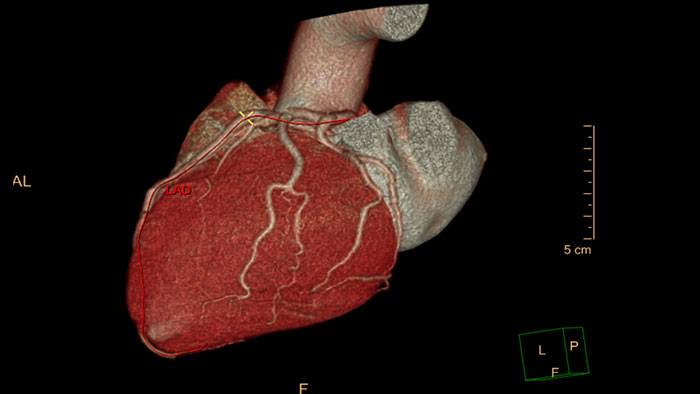

CT Comprehensive Cardiac Analysis (CCA)

Comprehensive cardiac analysis

Designed to assist the user in viewing, analyzing and quantifying dedicated Cardiac CT Angiograms, mainly for coronary arteries analysis on Coronaries CT Angiogram (CCTA) data.

Benefits

- Cardiac function measurements based on automatic 3D model-based whole-heart segmentation.

- Automatic extraction and visualization of the coronary tree.

- The user can edit and modify the segmentation and the derived parameters.